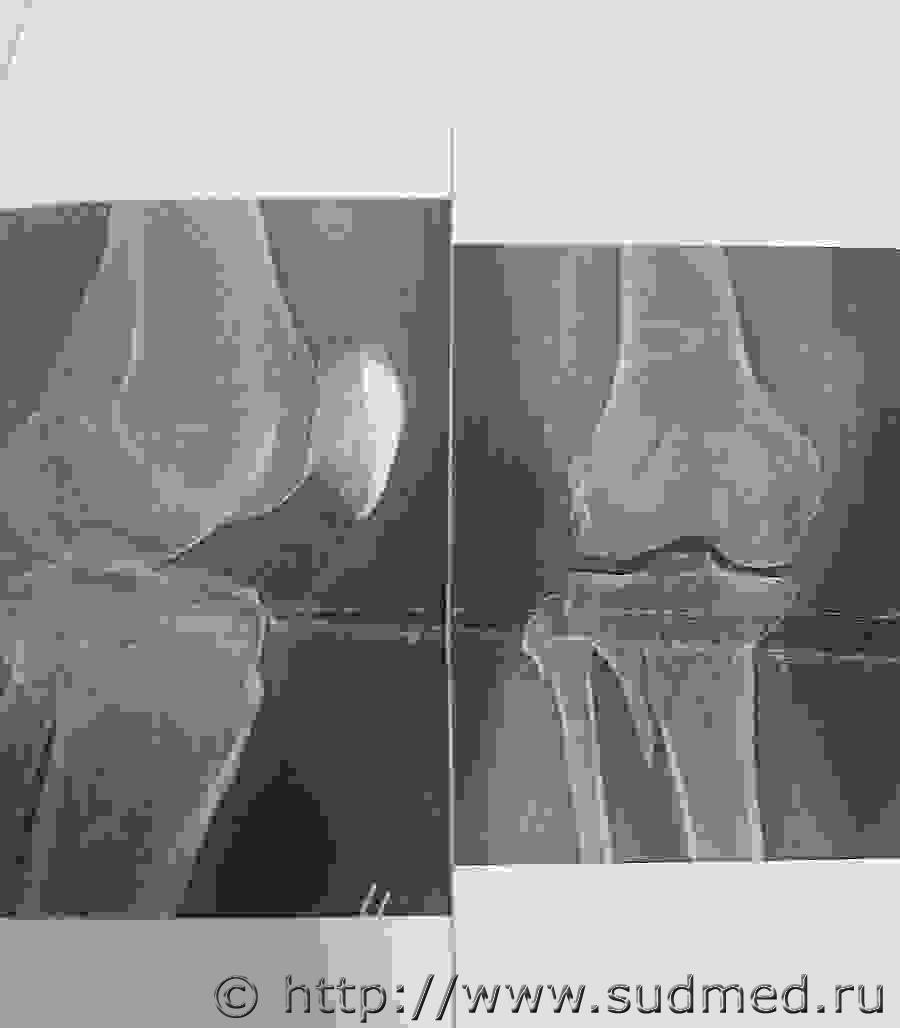

помогите, разобраться, есть ли тут перелом диафиза большеберцовой кости.Судебная медицина - Прикрепленное изображение

Вроде и похоже на то. Однако, я бы воздержался от выводов по такому вот изображению.

вот другое изображение.Судебная медицина - Прикрепленное изображение

Перелом захватывает диафиз.